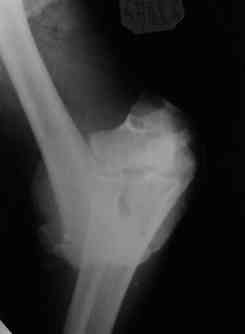

Открытый чрезмыщелковый перелом плеча |

Уважаемые коллеги! Мужчина, 49 лет, упал 2 недели назад, будучи около полугода в запое. Сразу припоступлении рана промыта а-ля пульсирующая струя" до 8 литров и стабилизация (без ушивания раны). Через 2 дня пациент покинул отделение, думаю, что сражался с рогатыми животными, еще через 4 дня победив всех врагов пришел как путный с поникшей головой. На настоящий момент рана с обильным гнойным отделяемым в виде комков, но повязка стала промокать меньше, температура субфебрильная 4 дня и выше 37,3 не поднималась, боли умеренные, больше ночью. Есть несколько вопросов: 1.Нужна ли сейчас ревизия и дебридмент? 2.Оптимальный вариант дренирования? (сейчас просто резиновые выпускники, в т.ч. через онтраппертуру). 3.Нижний стержень находиться в очаге. Его необходимо убрать? Если да, то вариант фиксации.Жалко свою работу. Может общими усилиями спасем? ;) Спасибо. С уважением, Алексей.

АМ> 3.Нижний стержень находиться в очаге. Его необходимо убрать? Если

АМ> да, то вариант фиксации.

Если нет нагноения его канала, то убирать его не надо. Однако фиксация не сильно надежная, может, хоть задней гипсовой шиной дополнить. Или наложить секцию на предплечье.